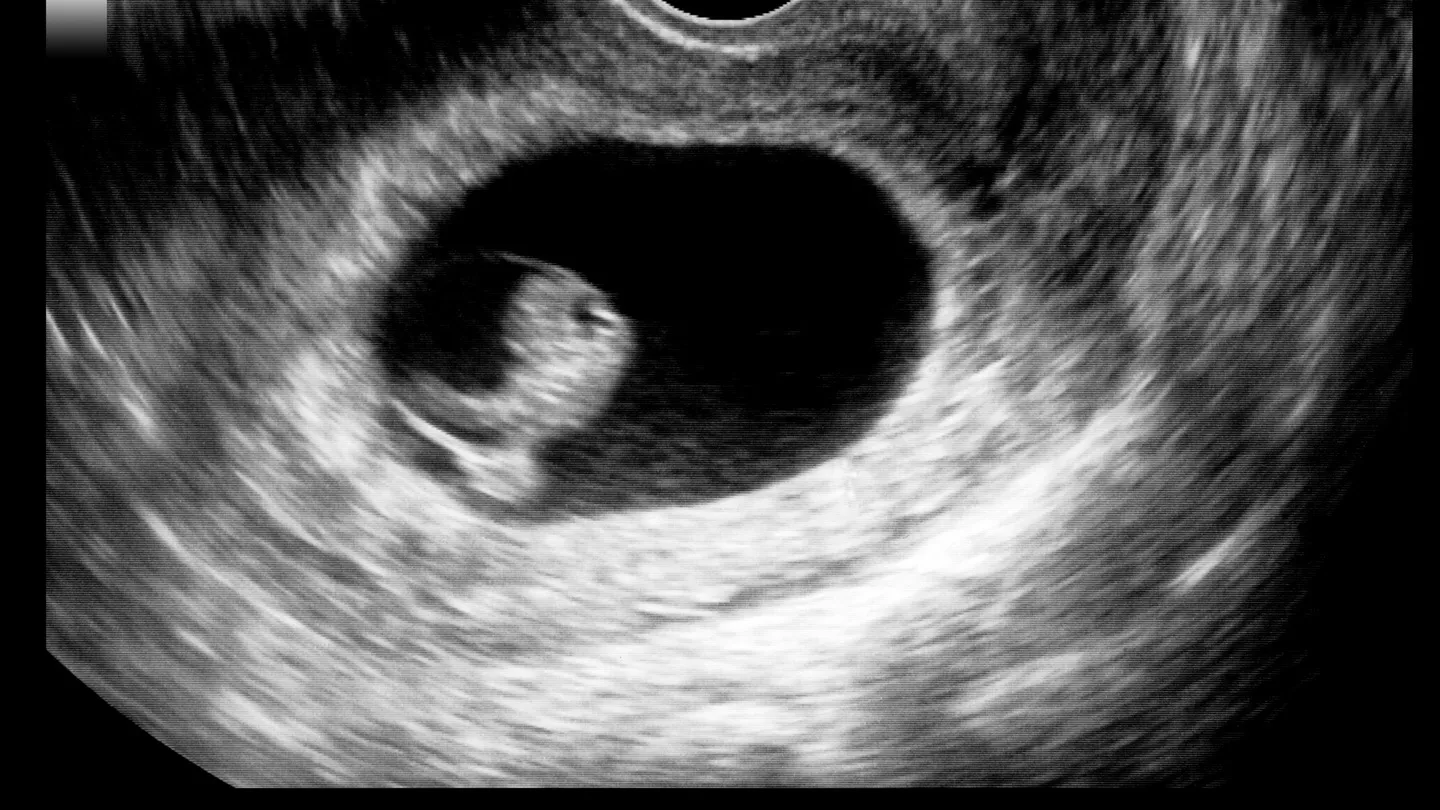

Процедуру переноса проводят под УЗИ-контролем, чтобы врач видел все, что происходит. Считается безболезненной, поэтому наркоз не применяется. Если женщина сильно нервничает, врач может дать ей седативное средство. Все манипуляции занимают 5-10 минут.

- Выпить стакан-полтора чистой воды за час до переноса, чтобы мочевой пузырь немного наполнился и гинекологу было удобнее при УЗИ-контроле.